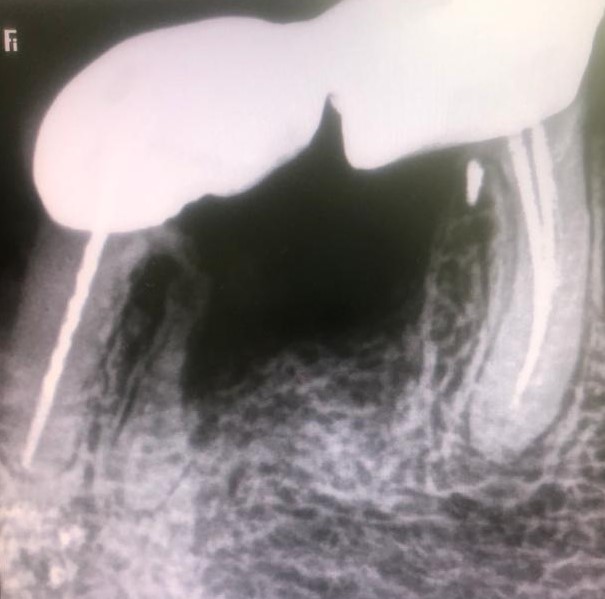

Presentamos un nuevo caso en el que la paciente presenta un gran dolor en su prótesis antigua (15 años) sobre dientes naturales tallados en zona inferior de molares. Es una paciente muy bruxómana, se unieron dos molares tallados con dos coronas. En el caso que presentamos el molar anterior estaba endodonciado ya antes de colocar la prótesis fija, pero el molar distal no. Y éste era la causa del gran dolor. Esto es por haberse filtrado creando caries y destrucción dentaria que llegaba al nervio. En conclusión, produciendo una gran pulpitis.

Esto provocaba en la paciente un gran dolor, pero ella no contemplaba en ese momento la opción de levantar la prótesis para explorar las piezas que había debajo, poder visualizar la destrucción dental y rehacer todo con una prótesis nueva. Por tanto, para quitar el dolor normalmente habría que haber hecho las extracciones de los dos molares, lo cual sería muy invalidante. En la clínica decidimos hacer una endodoncia de la raíz distal del último molar a través de la prótesis por la zona oclusal, y hacer odontosecciones de las raíces lesionadas sin quitar la prótesis. Ésta va permanecer tal como estaba.

Lo cierto es que las raíces  ya estaban bastante separadas de el resto de los molares correspondientes por su destrucción, lo que nos permitió la extracción de estas raíces en concreto. Teniendo en cuenta también que las raíces mesial y distal de cada molar no estaban unidas entre sí, sino que había una separación entre ellas.

La técnica quirúrgica para este menester es parecida a una apicectomía, pero en lugar de quitar solo el ápice radicular quitamos toda la raíz dental. Así pues lo que se hizo fue extracción de la raíz distal del primer molar y extracción de la raíz mesial del segundo molar. Con lo que la prótesis sigue teniendo dos pilares.